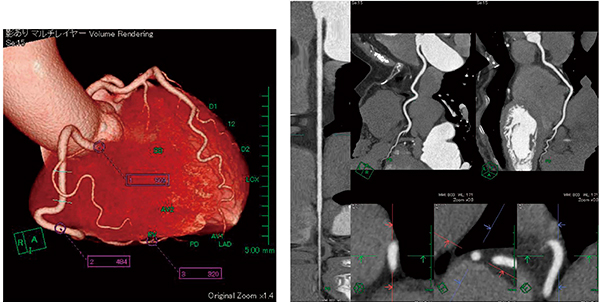

心臓CT(Dual ROI:音声ROI)

当院の心臓CTはDual ROI(音声ROI)撮影を基本としている。この撮影では,肺動脈・上行大動脈それぞれにROIを当て,肺動脈に閾値(100HU)を設定し,到達したら息止めの音声が流れる。そして,上行大動脈にも閾値(240HU)を設定し,到達した1〜2秒後に撮影する。

この撮影は,息止めをしてから数秒後に心拍数が下がることを考慮し,心拍数が最も安定し,同時に造影剤が個々の患者でピークに近いCT値からスキャンを開始することが可能になり,高濃染のときに撮影できる利点がある。

“新・CT細血管解析”では,造影剤が高濃染であることから自動追跡機能で冠動脈3枝の血管認識が直ちに可能で,その後は分岐点変更をしてから中心移動をすることにより血管のストレート表示がスムーズに行えるので,狭窄の有無の判断がすぐにできる。特に重宝している機能がsliding thin slab MIPで,狭窄が疑われる部分では必ずスラブ厚を変更しながら狭窄確認を行っている(図7)。

図7 右冠動脈の解析

右冠動脈の起始部で約510HU,#3で約480HU,#4PDで約320HUと高濃染であるため,画像は鮮明で構築しやすくなる